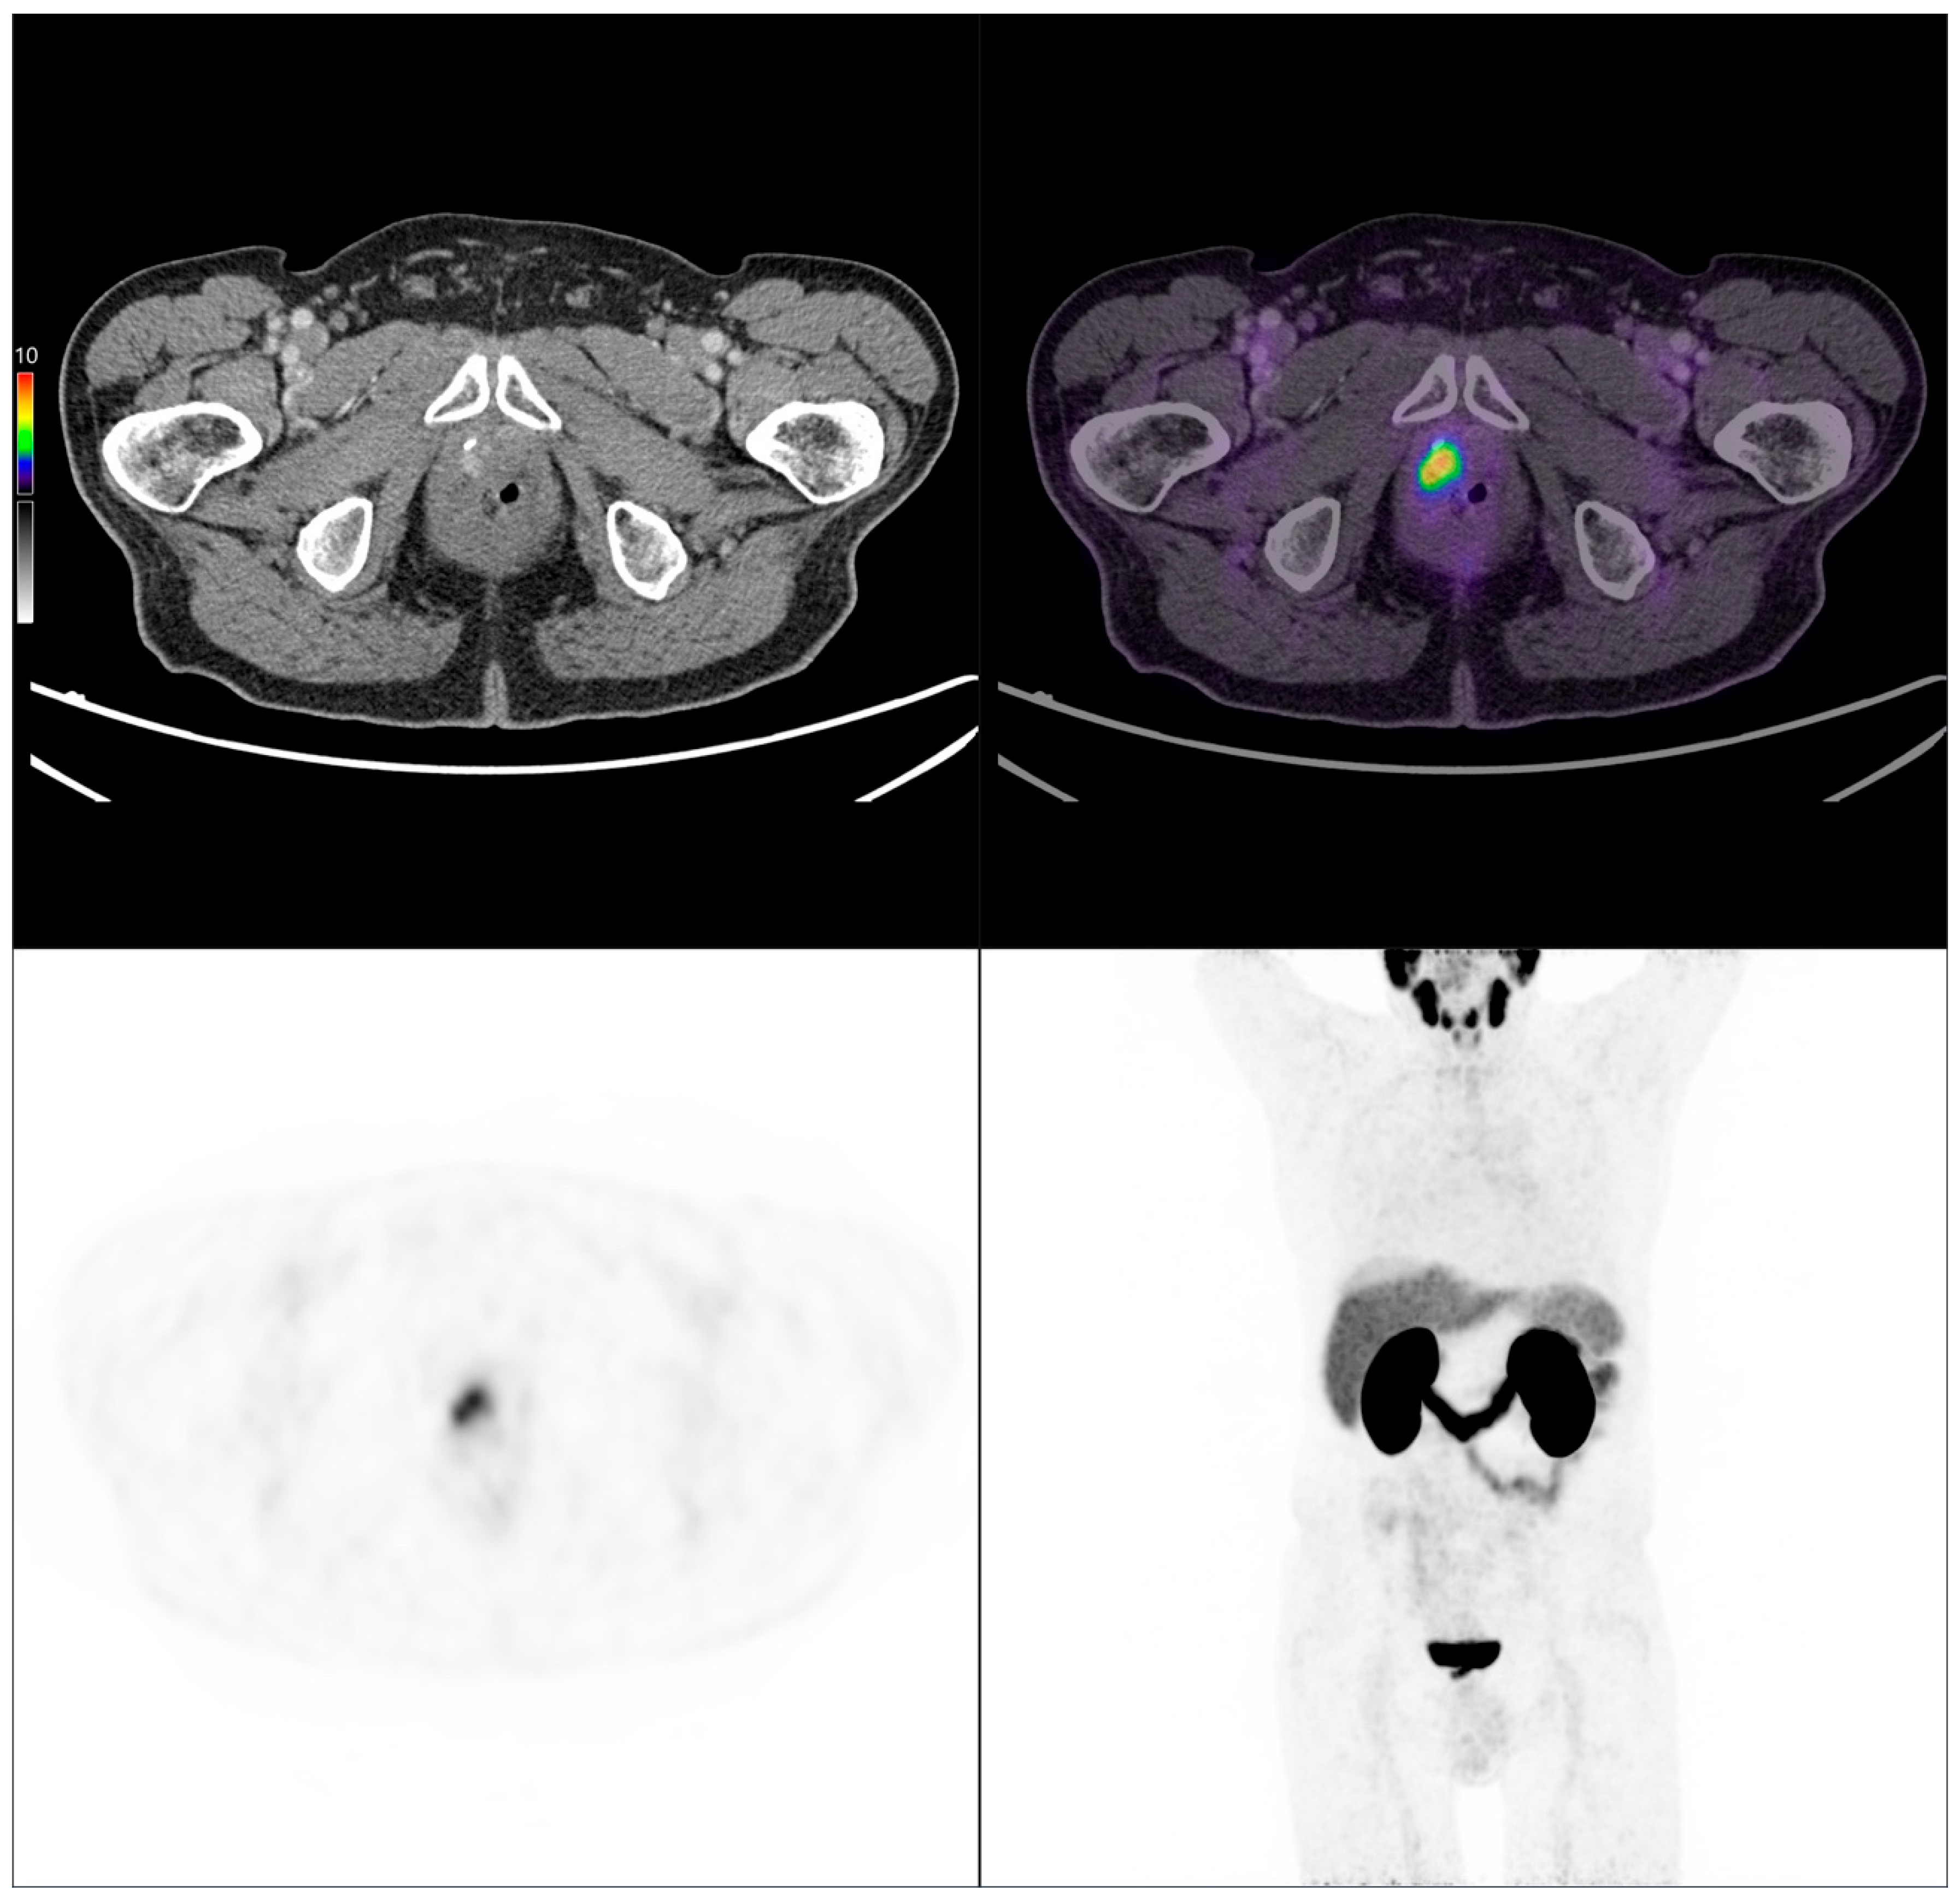

Figure 8.

PSMA PET/CT scan of an 84-year-old patient with biochemical recurrence (PSA: 0.67 ng/mL). Initially, the Gleason score was 4 + 3 = 7, pT3 pN0 M0, and treated with radical prostatectomy. Imaging performed following intravenous administration of 141 MBq of [68Ga]Ga-PSMA-11 revealed a local recurrence.